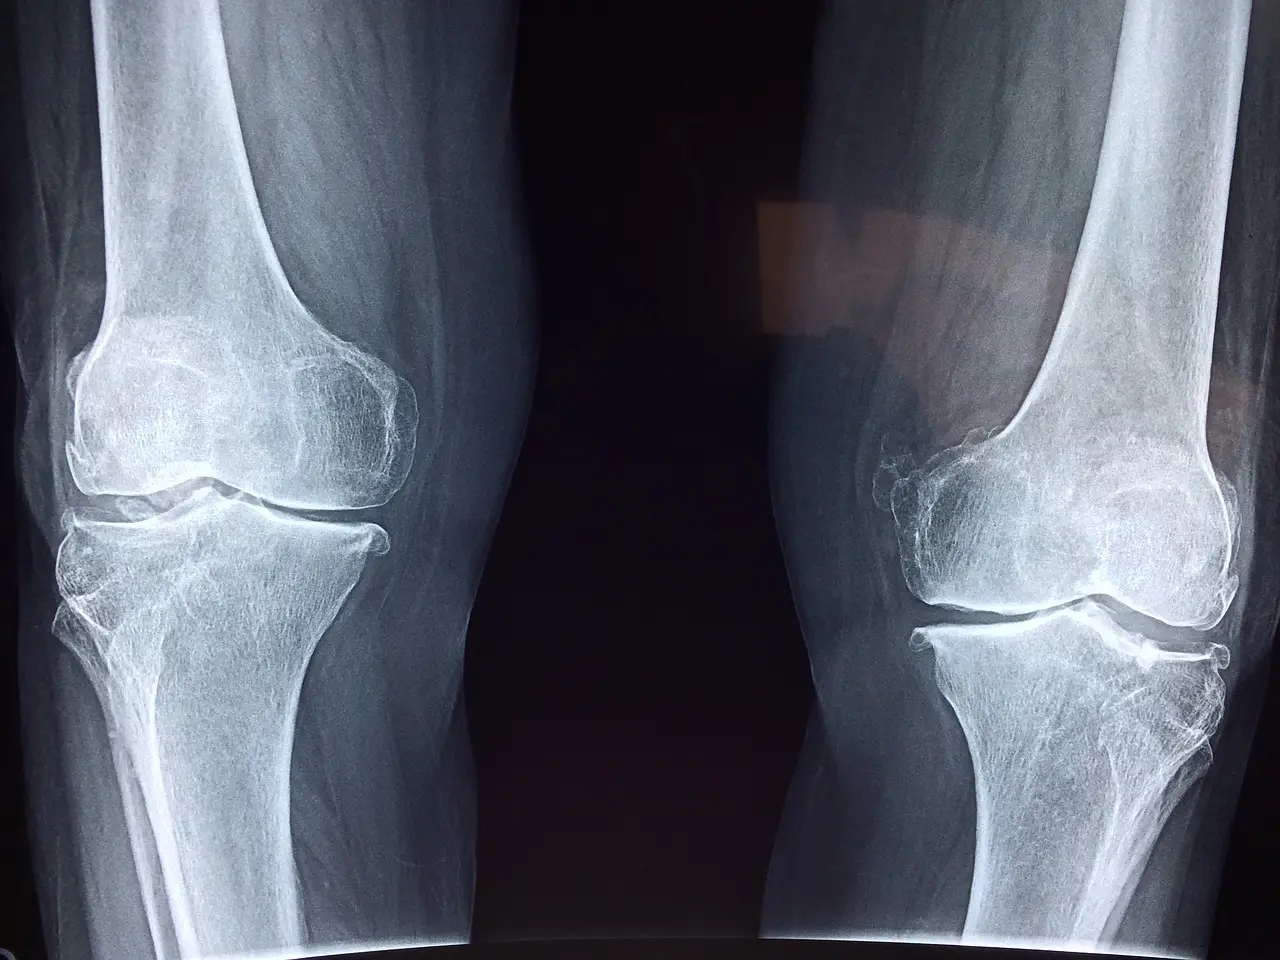

관절건강 개선

연골은 뼈사이에 쿠션역할을 합니다. 하지만 연골이 점점 닳게 된다면 뼈와 뼈가 마찰이 일어나 통증을 유발하게 됩니다. 콜라겐을 섭취하여 연골에 도움을 주어 관절건강을 개선할 수가 있게 됩니다.

뼈건강 개선

우리 몸의 뼈는 칼슘과 인 등이 80%, 콜라겐이 20% 정도로 구성되어 있다고 합니다. 튼튼한 뼈를 위해서는 콜라겐 주위에 칼슘 등의 성분이 잘 결합이 되어 있어야 합니다. 이러한 작용들이 어렵게 되면 골다공증으로 이어질 가능성이 높다고 합니다.